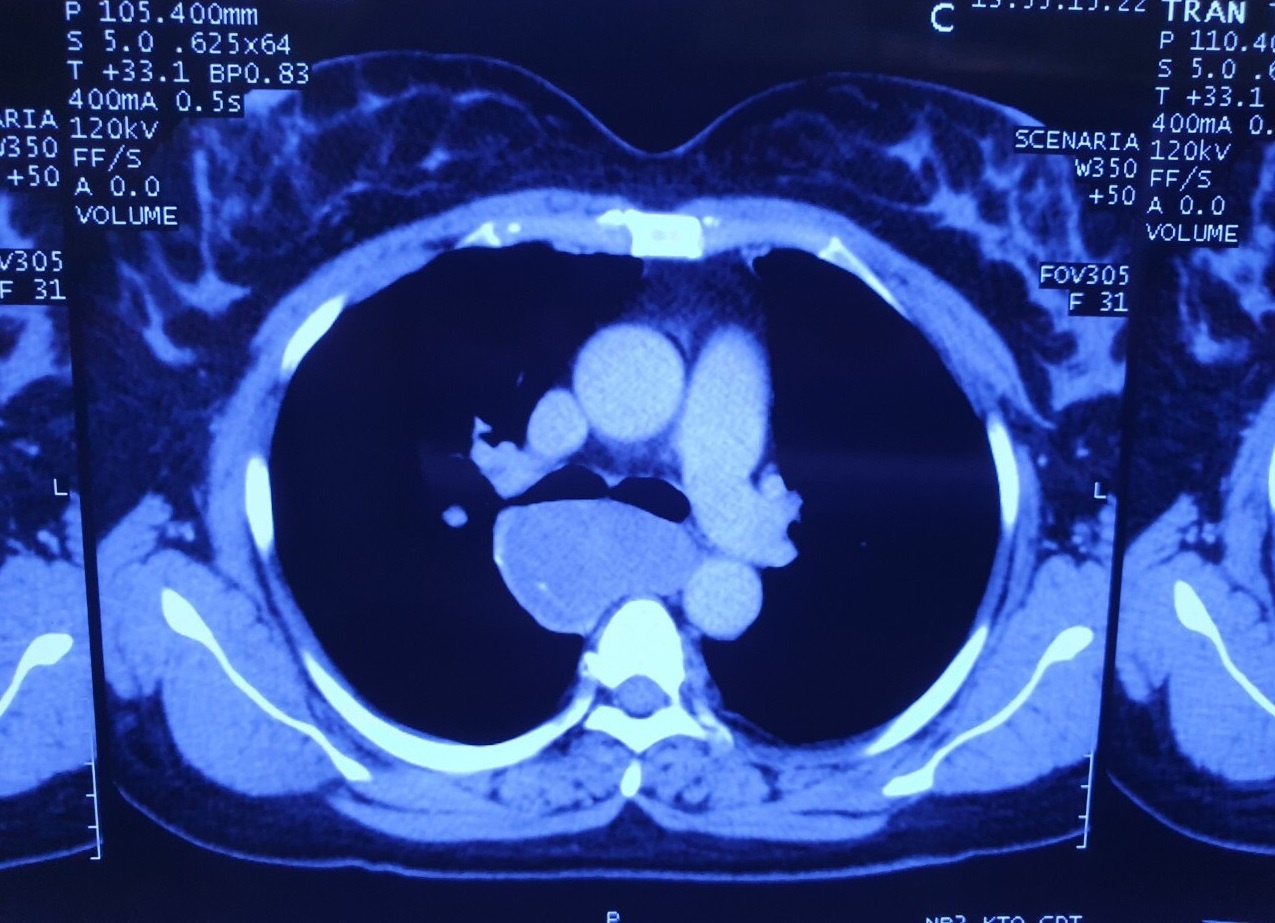

Sau khi được thăm khám, làm các chỉ định xét nghiệm, siêu âm, chụp CT lồng ngực và nội soi, các bác sĩ chẩn đoán bệnh nhân có u cơ lớn thực quản 8 cm ôm quanh thực quản 1/3 trên.

Các bác sĩ chẩn đoán bệnh nhân có u cơ lớn thực quản 8 cm ôm quanh thực quản 1/3 trên.